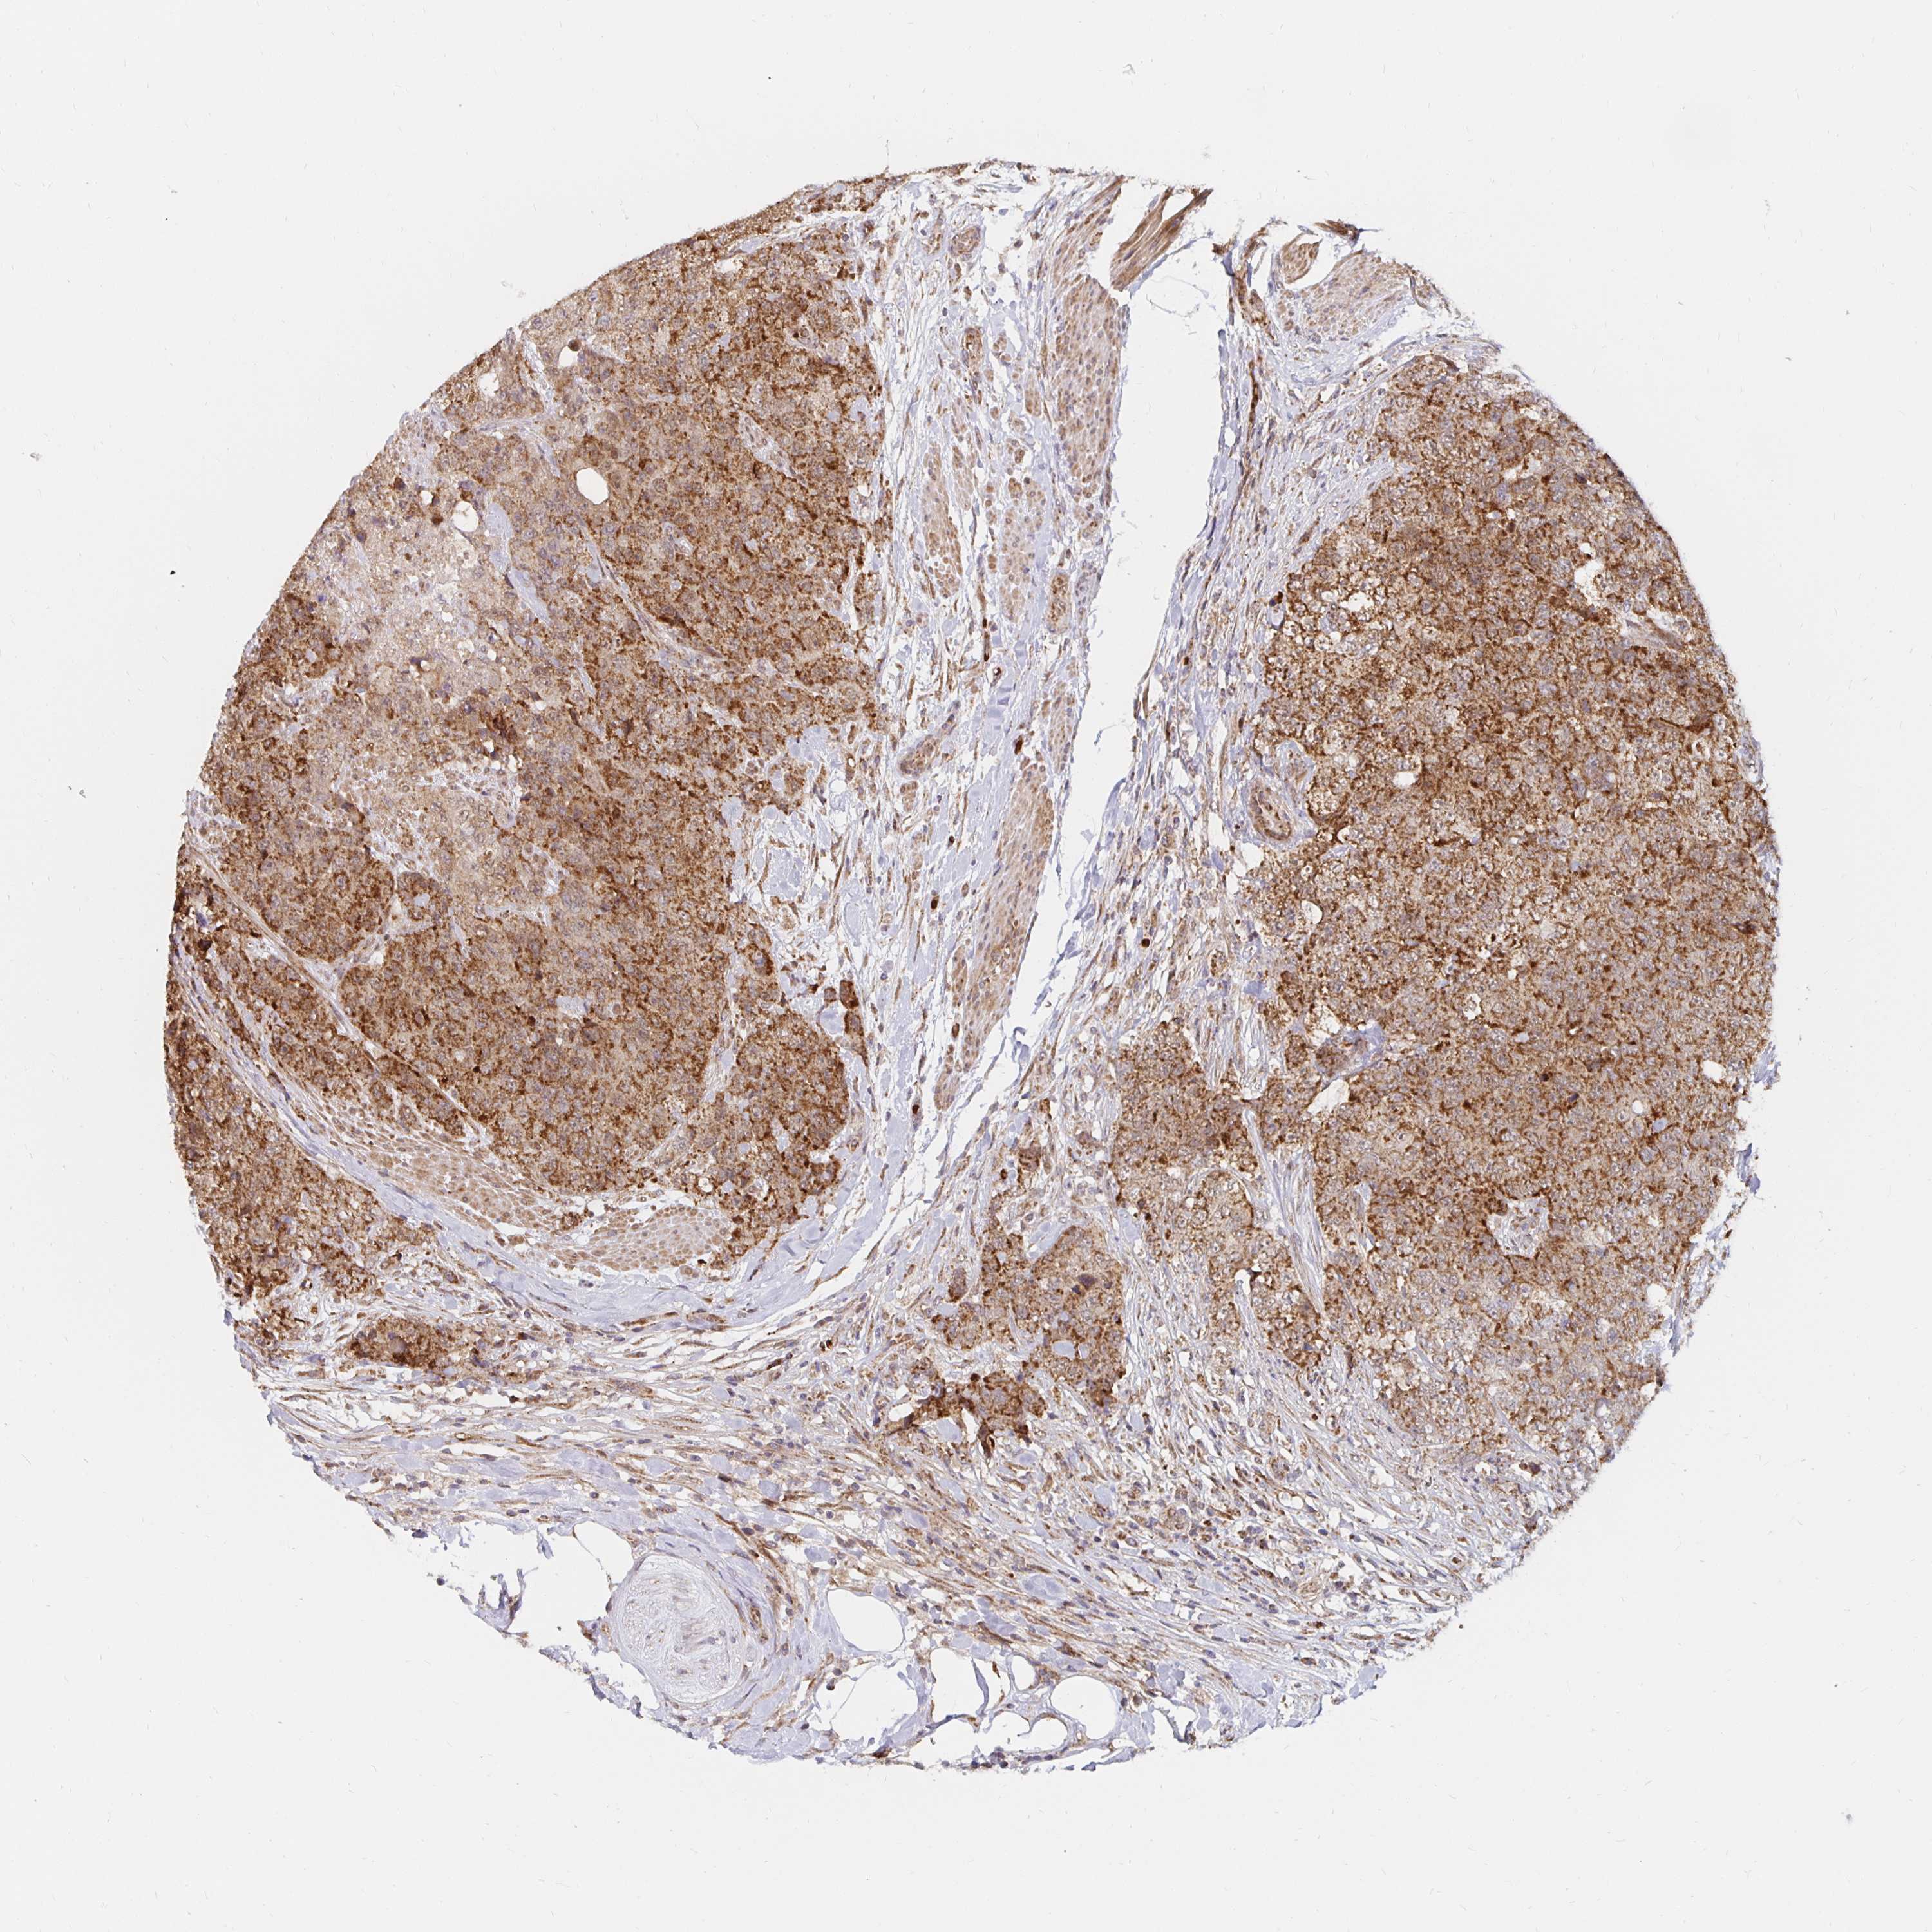

UROTHELIAL CANCER - Protein expressioni

A mouse-over function shows sample information and annotation data. Click on an image to view it in a full screen mode. Samples can be filtered based on level of antibody staining by selecting one or several of the following categories: high, medium, low and not detected. The assay and annotation is described here.

Note that samples used for immunohistochemistry by the Human Protein Atlas do not correspond to samples in the TCGA dataset.

Antibody stainingi

Antibody staining in the annotated cell types in the current human tissue is reported as not detected, low, medium, or high, based on conventional immunohistochemistry profiling in selected tissues. This score is based on the combination of the staining intensity and fraction of stained cells.

Each image is clickable and will lead to virtual microscopy that enables deeper exploration of all samples and also displays staining intensity scores, fraction scores and subcellular localization as well as patient and tissue information for each sample.

Antibody HPA030594

Antibody HPA055589

Antibody CAB033542

Staining

High

Medium

Low

Not detected

Intensity

Strong

Moderate

Weak

Negative

Quantity

>75%

75%-25%

<25%

None

Location

Nuclear

Cytoplasmic/membranous

Cytoplasmic/membranous,nuclear

Urothelial carcinoma, Low grade

Urothelial carcinoma, High grade

Urothelial carcinoma, NOS